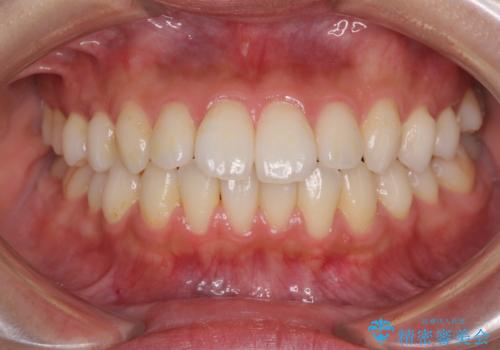

前歯の捻れを改善 インビザラインによる矯正治療